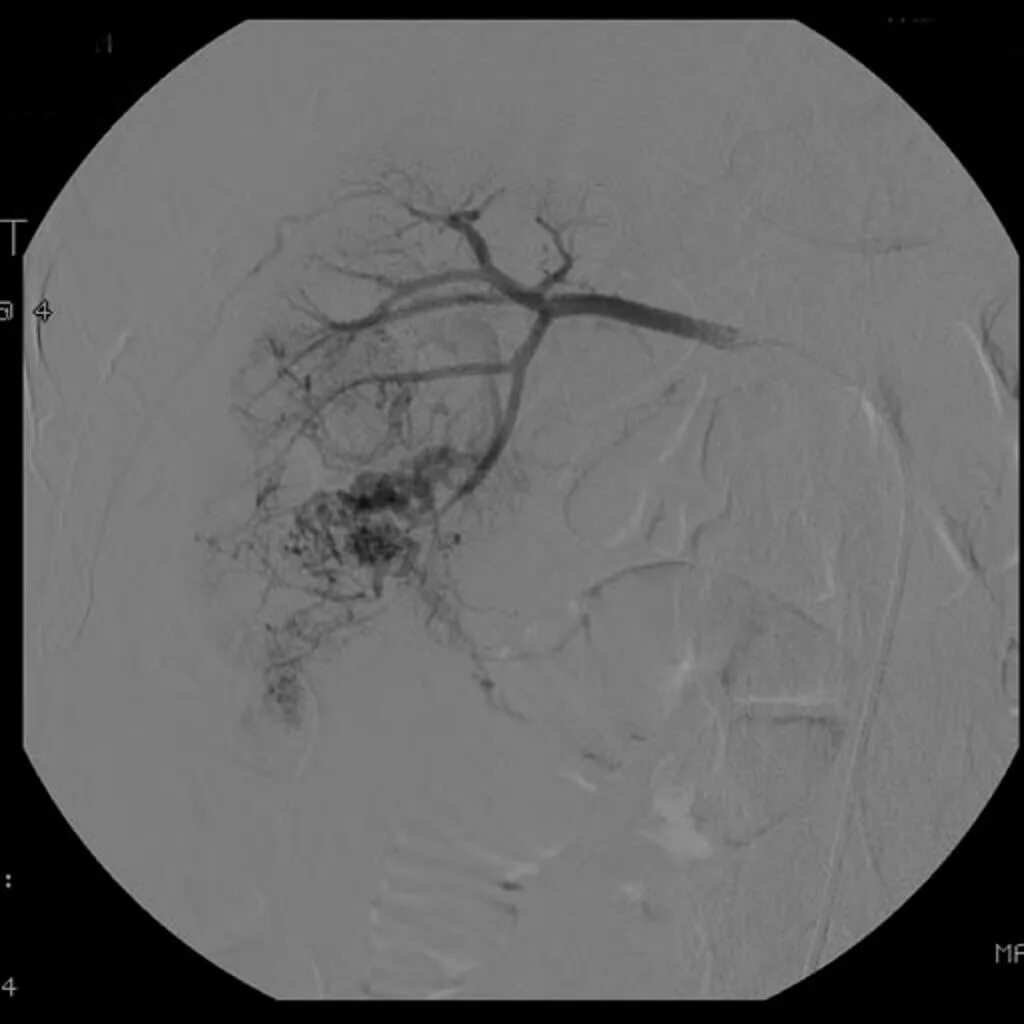

Эмболизация гемангиомы